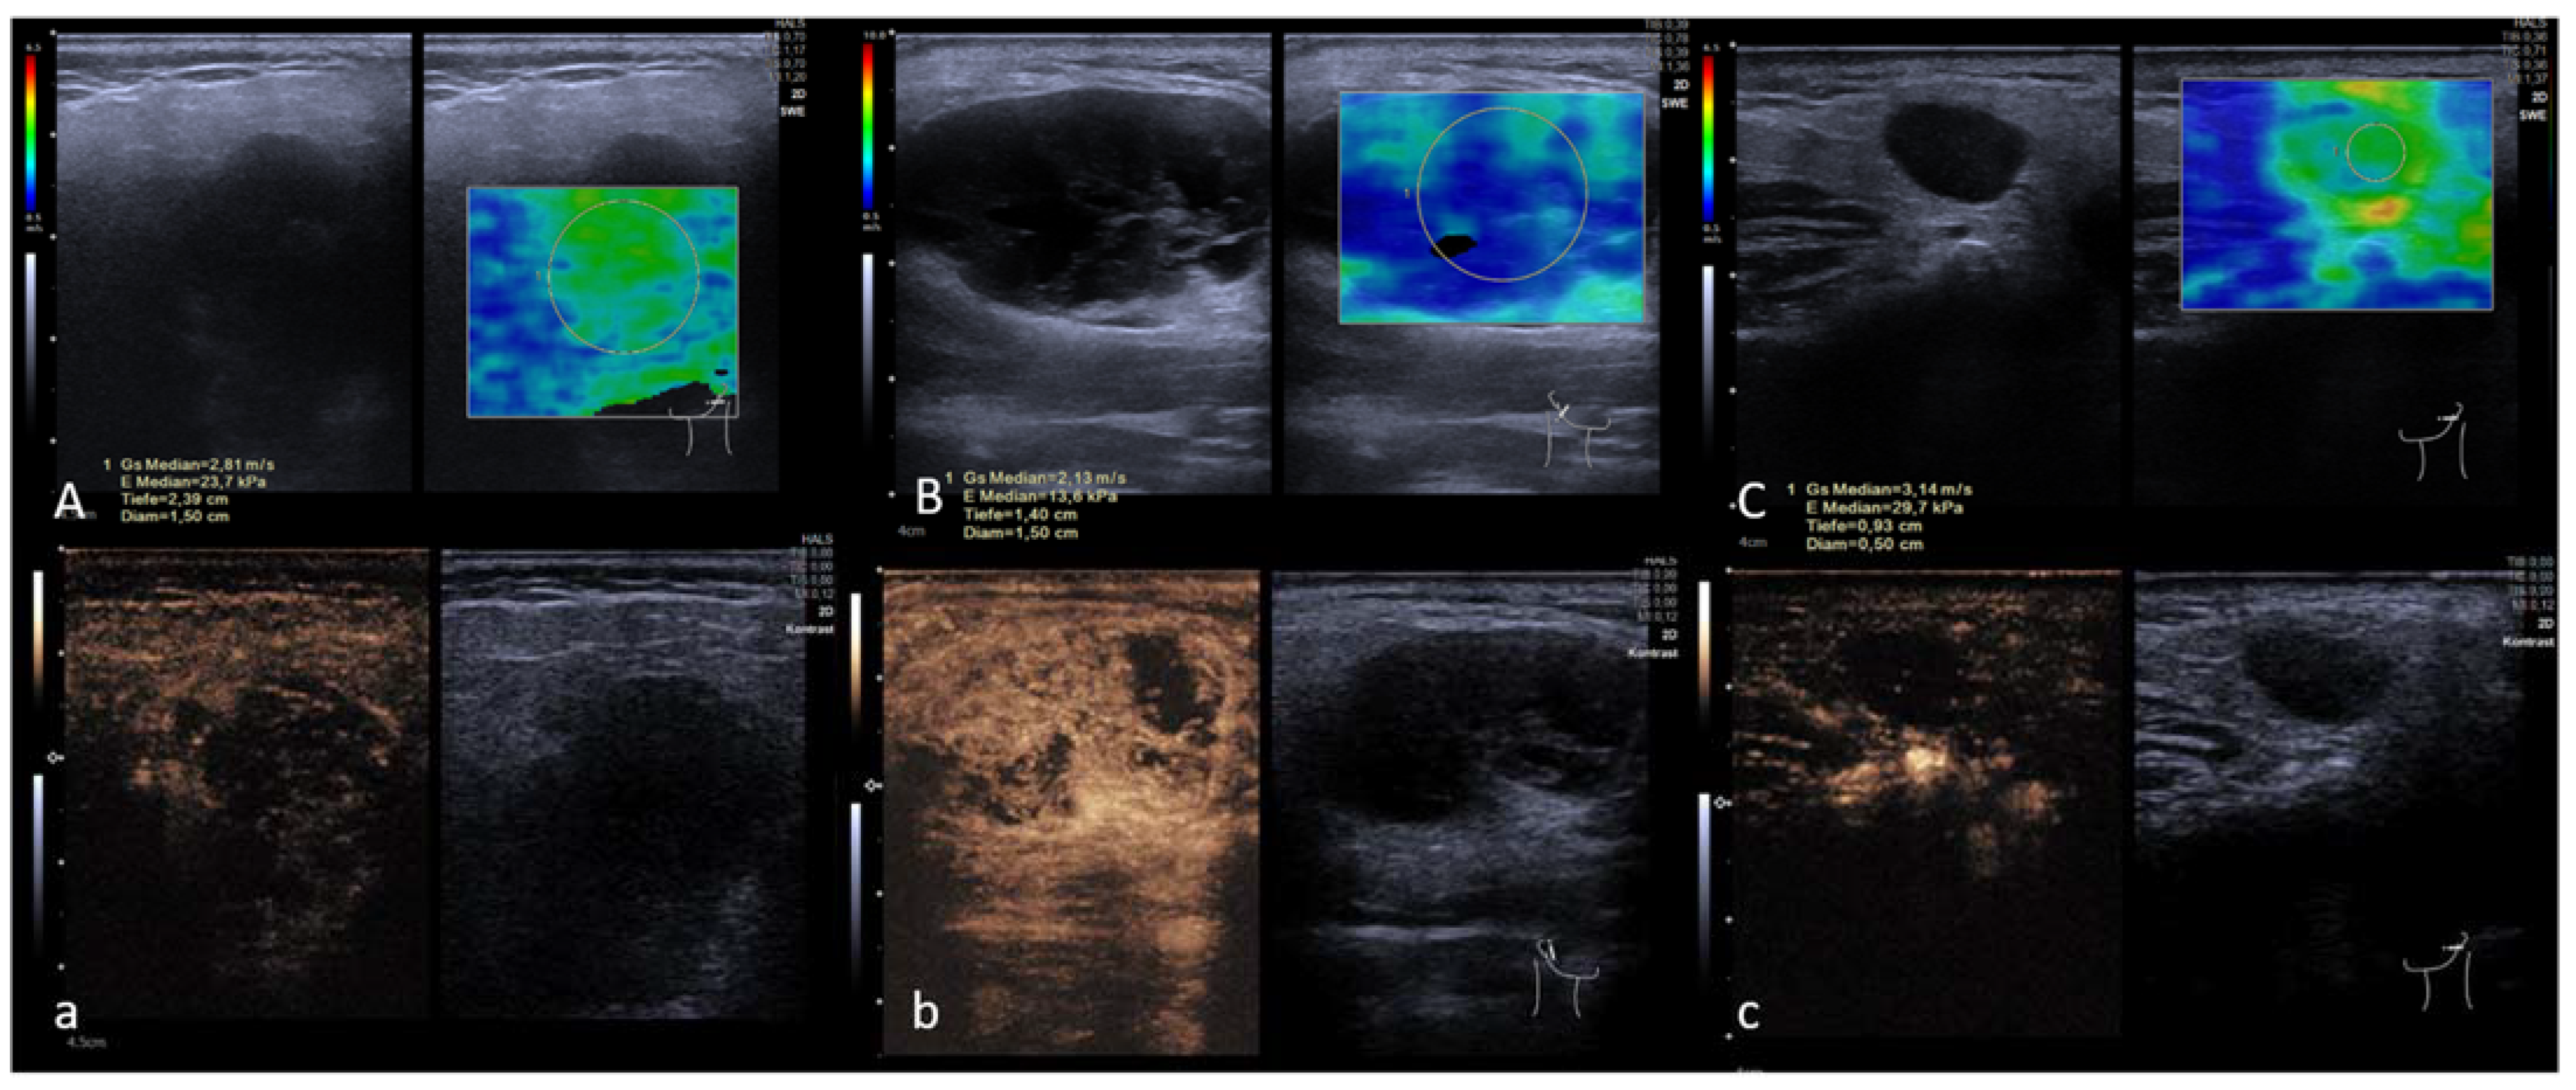

2.3. Shear Wave Elastography

2.4. Perfusion Analysis

3.4. CEUS